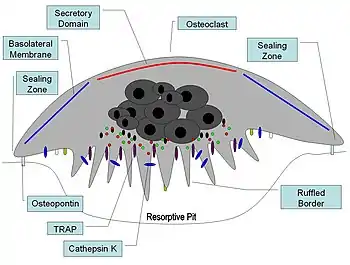

Illustration showing a single osteoclast | |

Osteoclasts are found on those surfaces of bone that are undergoing resorption. On such surfaces, the osteoclasts are seen to be located in shallow depressions called resorption bays (Howship's lacunae). The resorption bays are created by the erosive action of osteoclasts on the underlying bone. The border of the lower part of an osteoclast exhibits finger-like processes due to the presence of deep infoldings of the cell membrane; this border is called ruffled border. The ruffled border lies in contact with the bone surface within a resorption bay. The periphery of the ruffled border is surrounded by a ring-like zone of cytoplasm which is devoid of cell organelles but is rich in actin filaments. This zone is called clear zone or sealing zone. The actin filaments enable the cell membrane surrounding the sealing zone to be anchored firmly to the bony wall of Howship's lacunae. In this way, a closed subosteoclastic compartment is created between the ruffled border and the bone that is undergoing resorption. The osteoclasts secrete hydrogen ions, collagenase, cathepsin K and hydrolytic enzymes into this compartment. Resorption of bone matrix by the osteoclasts involves two steps: (1) dissolution of inorganic components (minerals), and (2) digestion of organic component of the bone matrix. The osteoclasts pump hydrogen ions into subosteoclastic compartment and thus create an acidic microenvironment, which increases solubility of bone mineral, resulting in the release and re-entry of bone minerals into the cytoplasm of osteoclasts to be delivered to nearby capillaries. After the removal of minerals, collagenase and gelatinase are secreted into the subosteoclastic compartment. These enzymes digest and degrade collagen and other organic components of decalcified bone matrix. The degradation products are phagocytosed by osteoclasts at the ruffled border. Because of their phagocytic properties, osteoclasts are considered to be a component of the mononuclear phagocyte system (MPS). The activity of osteoclasts is controlled by hormones and cytokines. Calcitonin, a hormone of thyroid gland, suppresses the osteoclastic activity. The osteoclasts do not have receptors for parathyroid hormone (PTH). However, PTH stimulates the osteoblasts to secrete the cytokine called osteoclast-stimulating factor, which is a potent stimulator of the osteoclastic activity.[1]

At a site of active bone resorption, the osteoclast forms a specialized cell membrane, the "ruffled border", that opposes the surface of the bone tissue. This extensively folded or ruffled border facilitates bone removal by dramatically increasing the cell surface for secretion and uptake of the resorption compartment contents and is a morphologic characteristic of an osteoclast that is actively resorbing bone.

Once activated, osteoclasts move to areas of microfracture in the bone by chemotaxis. Osteoclasts lie in small cavities called Howship's lacunae, formed from the digestion of the underlying bone. The sealing zone is the attachment of the osteoclast's plasma membrane to the underlying bone. Sealing zones are bounded by belts of specialized adhesion structures called podosomes. Attachment to the bone matrix is facilitated by integrin receptors, such as αvβ3, via the specific amino acid motif Arg-Gly-Asp in bone matrix proteins, such as osteopontin. The osteoclast releases hydrogen ions through the action of carbonic anhydrase (H2O + CO2 → HCO3− + H+) through the ruffled border into the resorptive cavity, acidifying and aiding dissolution of the mineralized bone matrix into Ca2+, H3PO4, H2CO3, water and other substances. Dysfunction of the carbonic anhydrase has been documented to cause some forms of osteopetrosis. Hydrogen ions are pumped against a high concentration gradient by proton pumps, specifically a unique vacuolar-ATPase. This enzyme has been targeted in the prevention of osteoporosis. In addition, several hydrolytic enzymes, such as members of the cathepsin and matrix metalloprotease (MMP) groups, are released to digest the organic components of the matrix. These enzymes are released into the compartment by lysosomes. Of these hydrolytic enzymes, cathepsin K is of most importance.

Upon polarization of the osteoclast over the site of resorption, cathepsin K is secreted from the ruffled border into the resorptive pit. Cathepsin K transmigrates across the ruffled border by intercellular vesicles and is then released by the functional secretory domain. Within these intercellular vesicles, cathepsin K, along with reactive oxygen species generated by TRAP, further degrades the bone extracellular matrix.

The effectiveness of its ion secretion depends upon the osteoclast forming an effective seal around the resorption compartment. The positioning of this "sealing zone" appears to be mediated by integrins expressed on the osteoclast surface.[20] With the sealing zone in place, the multinucleated osteoclast reorganizes itself. Developing the highly invaginated ruffled membrane apposing the resorption compartment allows massive secretory activity. In addition, it permits the vesicular transcytosis of the mineral and degraded collagen from the ruffled border to the free membrane of the cell, and its release into the extracellular compartment.[21][22] This activity completes the bone resorption, and both the mineral components and collagen fragments are released to the general circulation.